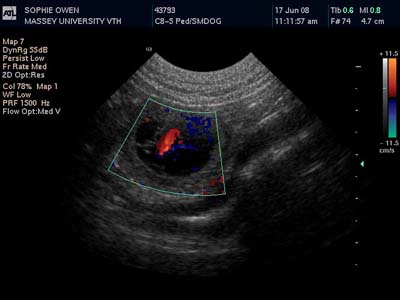

17th June 2008 - Sophie had her ultrasound today and is definitely pregnant!

The arrow points to the puppy's heart.

The two colours show the two directions of bloodflow.

This image shows two puppies!